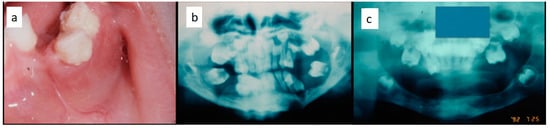

Nine patients were affected by single eosinophilic granuloma of the mandible and two of the maxilla (0–10 A; 10–18 C). Inflamed, hyperplastic, painful and often ulcerated gingival lesions were common findings in 22 cases (0–10 A; 10–18 B) (Figure 1). They were associated with deciduous teeth mobility and/or dislocation with gingival probing and periodontal bone loss in 18 cases, and to premature teeth loss with dislocation of the permanent teeth follicles and bone lesions (single or multiple) in nine cases (0–10 B; 10–18 A) (Figure 2a–d). Focal gingival swelling (often with superficial ulceration) occurred in patients with single lesion of the jaws (five in the maxilla and three in the mandible), all appearing as radiolucency with well-defined borders but, however, with rapid bone erosion (0–10 A; 10–18 C). Single lesions of the palatal mucosa were detected as the first sign in six patients (0–10 A; 10–18 B), generally appearing as reddish or strawberry gingivitis with periodontal involvement and/or complete diffusion to the palate (0–10 C; 10–18 B) (Figure 3a,b). Nine patients showed diffuse lesion of the mandible with a progressive resorption of the alveolar bone with the characteristic “floating teeth” appearance (0–10 B; 10–18 A); in six cases, localized lesions of the maxilla were synchronously detectable (0–10 C; 10–18 B) (Figure 4a,b). In addition, patients with periodontal involvement had in common a delayed diagnosis of several months as they received treatments for gingival/periodontal diseases but were unresponsive to each one. The resorption of dental roots has never been observed on either deciduous or permanent teeth. Paresthesia, due to compression of the inferior alveolar nerve, was observed in only three cases, while in six instances a pathological fracture of the mandible occurred (0–10 A; 10–18 C) (Figure 5a–c), both resulting in expansion of an osteolytic lesion. Submental, submandibular and lateral-cervical lymph nodes involvement was associated with oral lesions in 12 cases (0–10 B; 10–18 B). Adjunctive radiological examination revealed lesions of the skull in 14 patients and, respectively, two of the parietal bone (Figure 6a), two of the temporal bone, one of the zygomatic bone, and three of the orbit (0–10 B; 10–18 C). Otitis (media or externa) was referred or detected in four instances, cutaneous rush in nine (0–10 B; 10–18 C) (Figure 6b), exophthalmia in two (Figure 7a,b), while data about the contextual presence or subsequent onset of insipidus diabetes were available only in eight cases (0–10 B; 10–18 C).

Figure 3. (a,b): Diffuse infiltration of the palatal mucosa with strawberry appearance as the first manifestation of LCH (a); complete regression after medical therapy (b).

Figure 5. (ac): Diffuse periodontal lesions in the mandible in a 5 year-old female patient causing teeth mobility with pathological fracture and dislocation on the left side (a,b); panoramic radiograph after medical and functional treatment (c).